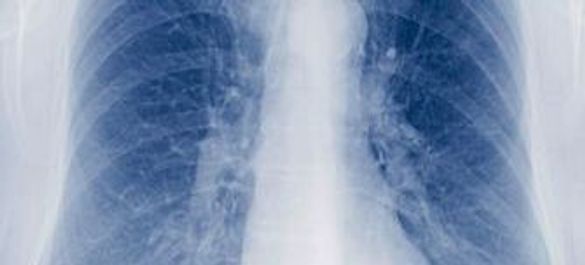

Tuberculosis Explainer

Tuberculosis is a bacterial disease that caused illness in an estimated 8.8 million people globally in 2010 and led to 1.45 million deaths.